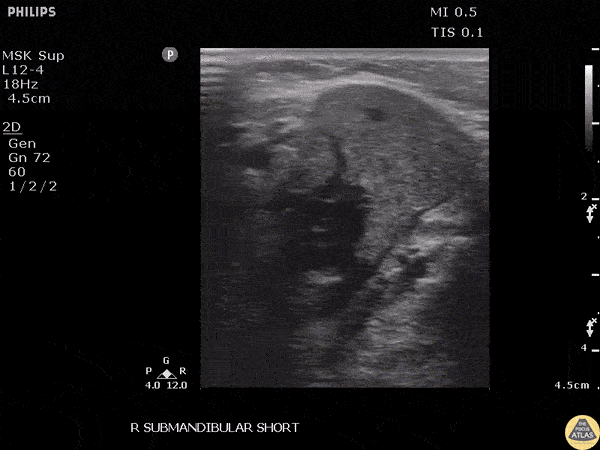

Soft Tissue - Submandibular Sialolithiasis

Patient with submandibular swelling was found to have a stone obstructing the submandibular duct, noted as a hyperechoic structure. Image courtesy of Robert Jones DO, FACEP @RJonesSonoEM Director, Emergency Ultrasound; MetroHealth Medical Center; Professor, Case Western Reserve Medical School, Cleveland, OH View his original post here